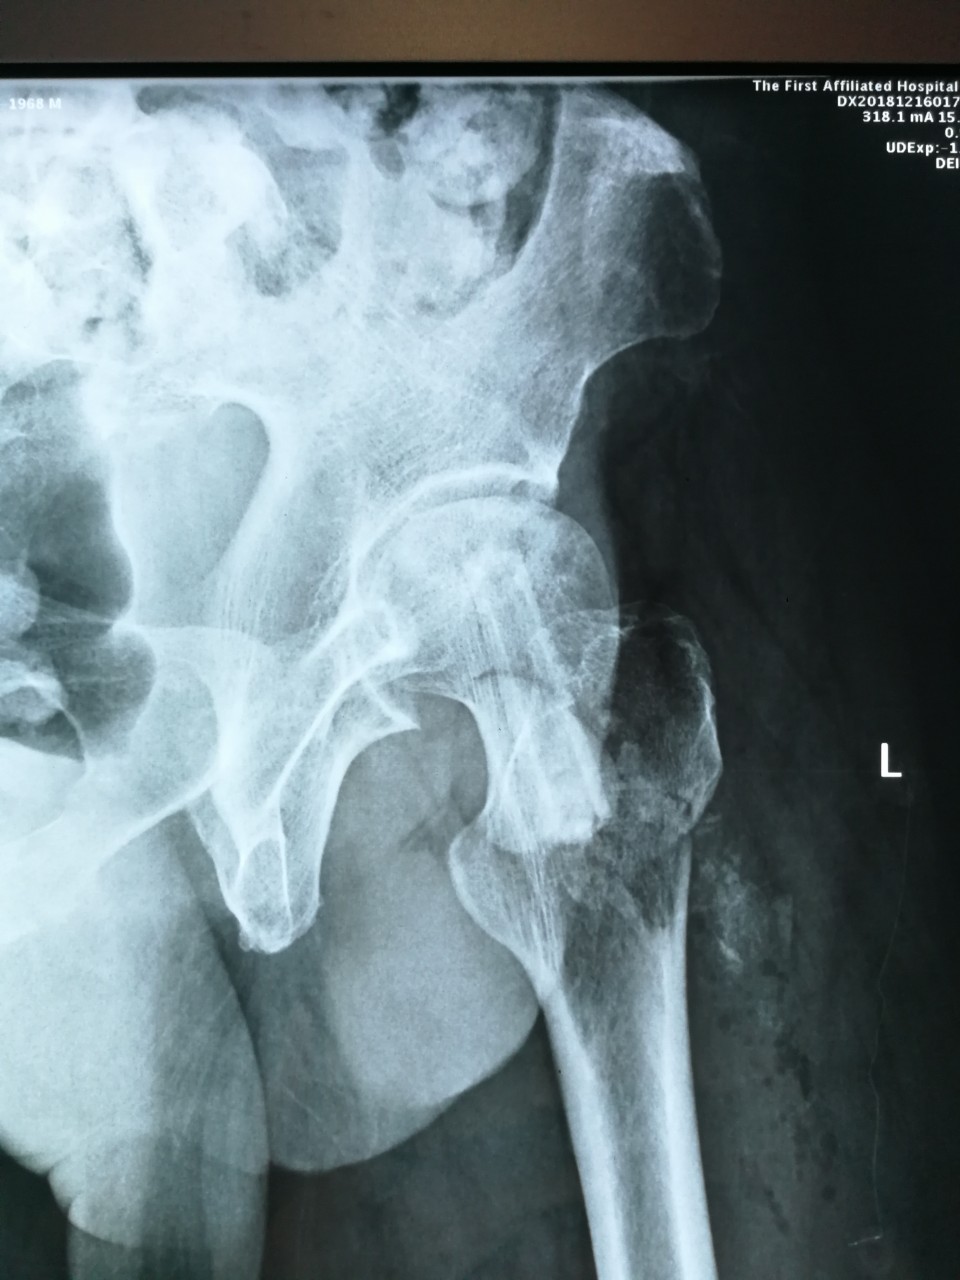

近日,我院创伤骨科病区王刚主任团队利用“天玑”骨科机器人成功为一名股骨头坏死患者施行“机器人导航辅助微创股骨头病灶清除减压+游离腓骨移植术”,患者术后恢复良好,已顺利出院。

股骨头坏死是临床常见疾病之一,常见病因为股骨颈骨折、激素、酗酒等,若早期不进行干预治疗,一旦发生股骨头塌陷,将严重影响行走及日常生活,残疾率高,最终需行髋关节置换术。青壮年早期股骨头坏死的保髋治疗有效率在80%以上,目前国内主流的治疗方法是股骨头病灶清除减压+游离腓骨移植术,但是传统手术手术切口大,病灶定位需要大量射线透视,且不够精确,存在较大局限性。此次创伤骨科王刚主任团队,充分发挥我院“天玑”骨科机器人的优势,利用机器人导航精准定位股骨头坏死中心,再通过小切口进行自体腓骨移植,无需传统内固定辅助,极大地降低了患者费用,减少了术中辐射量。